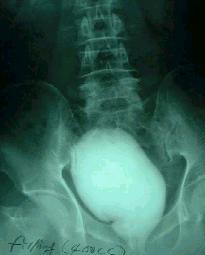

¼ö¼úÈÄ »õ·Î ¸¸µç ¹æ±¤¸ð¾ç »çÁø